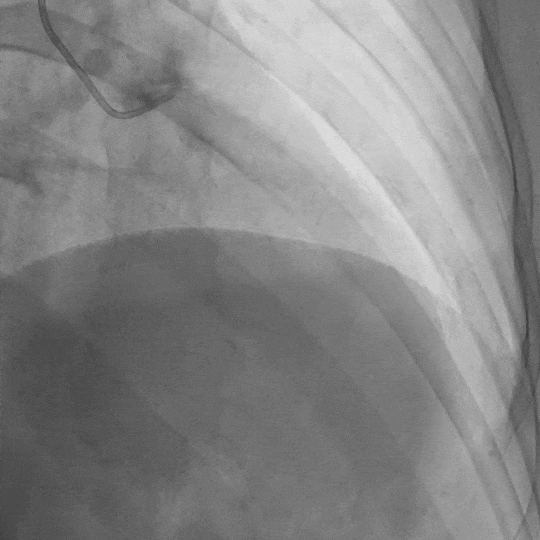

影像素材 | 患者冠状动脉造影 1:前降支中段长段心肌桥,收缩期管腔重度狭窄

影像素材 | 患者冠状动脉造影 2:前降支中段长段心肌桥,收缩期管腔重度狭窄